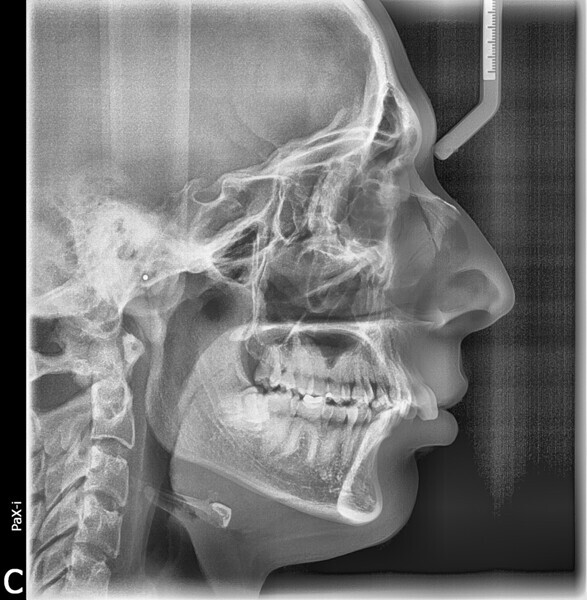

In the radiographic analysis, the dental panoramic tomogram revealed that the two mandibular third molars were unerupted and horizontalised in the mandible. Nothing else relevant was observed in the radiograph (Fig. 3). A cephalometric radiograph was used to perform the cephalometric analysis according to Steiner,6 Ricketts7, 8 and McNamara9 (NemoCeph Studio, Nemotec Fig. 4).

In the Steiner analysis, the SNB angle of 74° suggested mandibular retrusion. Likewise, the ANB angle of 7° indicated Class II, which was also confirmed by Wits analysis (8.3 mm). The results indicated a protrusion of the maxillary incisors and a decreased inter-incisal angle of 118°, which suggested protrusion of the maxillary and mandibular incisors (Fig. 5).

In the Ricketts analysis, a dolichofacial pattern, that is, a facial axis of 84°, was diagnosed. The analysis also confirmed the protrusion of the incisors (Fig. 6).

The McNamara analysis revealed that the size of the mandible that would correspond to the dimensions of the maxilla (91.0 mm) would be between 114.0 mm and 117.0 mm and not the current size of 111.9 mm,9 indicating that the mandible was smaller than it should have been. However, the maxillomandibular difference was 20.9 mm, indicating a Class II skeletal pattern (Fig. 7). From the aforementioned information, we determined a Class II skeletal pattern and dental relationship with retrusion of the lower jaw and an increased overjet and overbite.